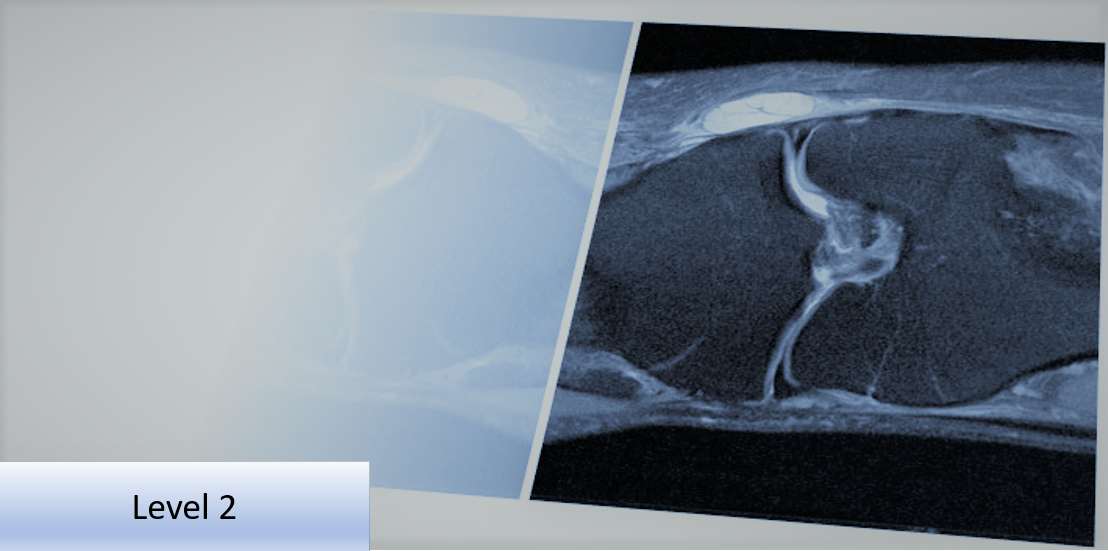

Level 2 Further Skills: Musculoskeletal Imaging Referral and Interpretation - Lower Limb

This Level 2 course will provide the delegate with further skills and understanding to improve diagnostic imaging use and ensure it is clinically appropriate, thereby supporting clinical examination of the lower limb.